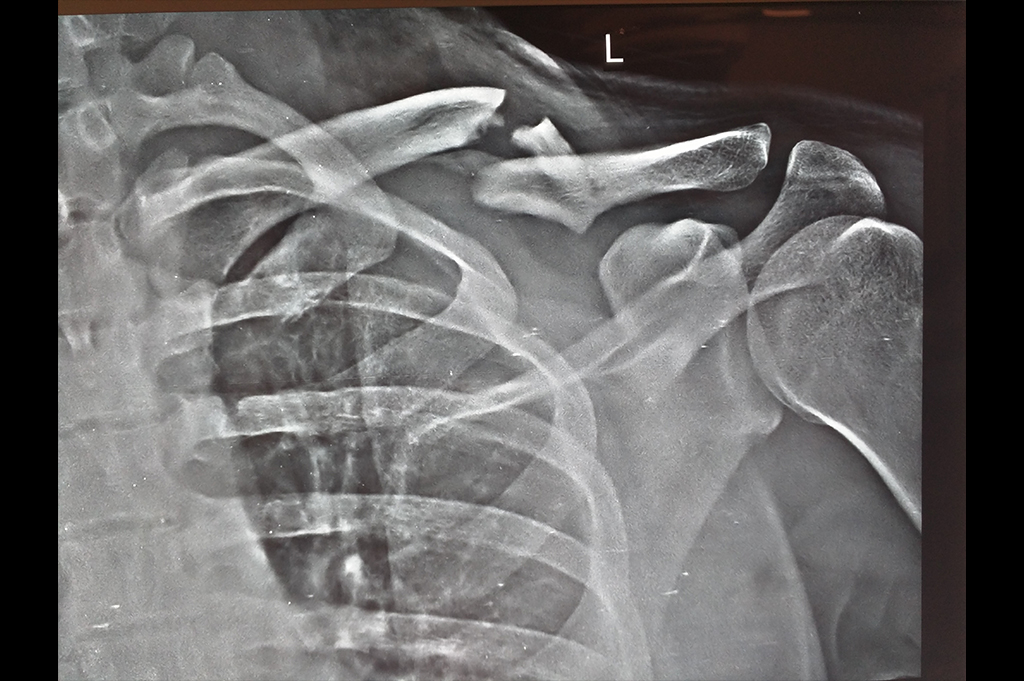

Proximal Humerus